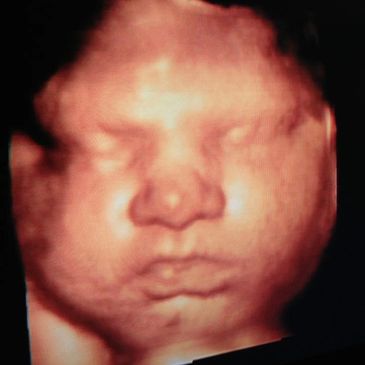

Experience the miracle of 3D/4D Ultrasound

This includes 2 color pictures in 3D/4D and 4 black and white pictures.